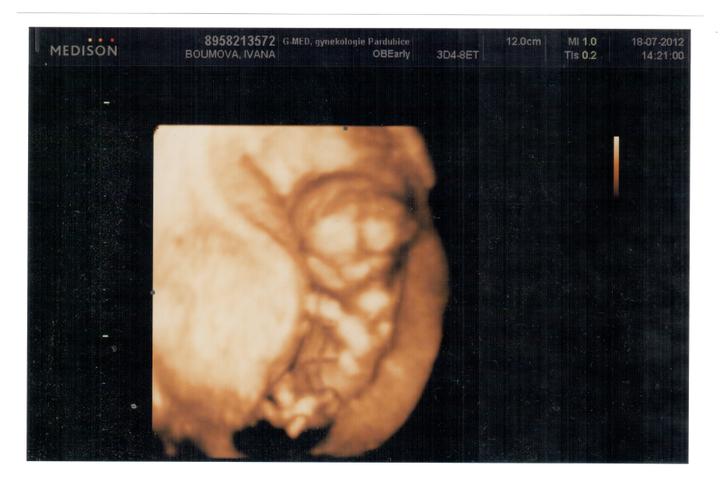

Holky, já se na tu naši Josefínku tak strašně těším 🙂)